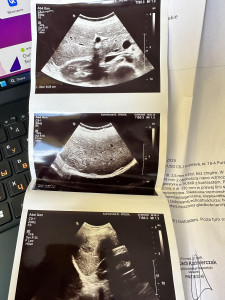

В 6/7 печени посткапсулярное поражение размером 40х30 мм, гипоинтенсивное на Т1, гиперинтенсивное на Т2. Показывает быстрое Периферическое усиление, за которым следует полное усиление контраста в очаге поражения в последующих фазах, с видимым вымыванием контраста через 1 час: Признаков опраничения диффузии нет. Изображение указывает на быстротекущую

гемангиому. На стр. 4b извилистость диаметром 4 мм с прилегающей зоной усиления диаметром 6 мм, что указывает на область нарушенной перфузии.

Заключение: Поражение правой доли печени указывает на быстроротекающую гемогиму, требующую наблюдения..

Повторное МРТ не является обязательным, если нет сомнений в заключении и очаг не изменяется, но при желании можно сделать его в крупном диагностическом центре для второго мнения. По фото УЗИ точно судить нельзя т.к фото снимка неинформативно, важно опираться на полное описание, где подробно указаны структура, эхогенность и кровоток образования.